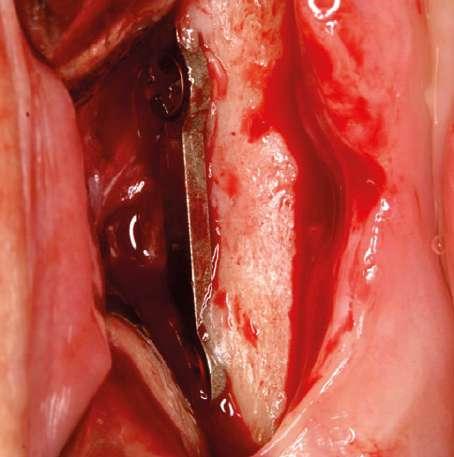

de colocación de las prótesis. La decisión de insertar tornillos de implante en la primera fase de la terapia vino dictada por la necesidad de realizar una cirugía ósea regenerativa que requiere tiempos de cicatrización bastante largos. A la espera de la osteointegración, se llevarán a cabo terapias orientadas a restaurar el maxilar superior con prótesis. Se insertaron cuatro fijaciones de implantes Mesa en el arco inferior, dos en el cuarto cuadrante y dos en el tercer cuadrante con una técnica de regeneración ósea asociada, teniendo en cuenta la

calidad y cantidad ósea, el grosor de los tejidos blandos, los puntos de referencia anatómicos y el tipo, volumen y forma de la restauración final. La presencia de un hueso de tipo D1-D2 hizo necesario utilizar, además de las fresas específicas presentes en el sistema de implantes, machos de rosca que correspondieran a la sección del implante escogido. El uso de machos de rosca evita que los implantes se introduzcan en el lugar preparado con fuerzas elevadas (superiores a 70 Newtons) que podrían comprometer la integridad de la conexión protésica.(Fig. 7, 8, 9, 10). 5

Figura 9. Colocación del implante y preparación del protocolo de regeneración ósea.

Figura 10. Implantes colocados, con la membrana de pericardio in situ, antes de la fijación y sutura. Figura 8. Detalle de la fase de preparación del lecho implantario. Figura 11. Radiografías intraorales realizadas al final de la fase quirúrgica.